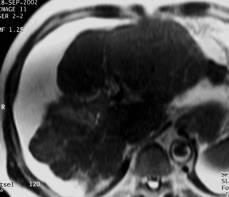

Patient suivi pour une cirrhose alcoolique. L'IRM est réalisée dans le cadre d'un bilan pré greffe.adressé pour bilan pré greffe.Vascularisation

Séquence pondérée T2, T1 Injection de gadolinium phase artérielle portale et tardive à 5 mn |

Vascularisation hétérogène du foie : nudule hypervasculaire à la phase artérielle (CHC), réhaussement locorégional à la phase portale ( vol vasculaire) et rehaussement tardif de la fibrose confluente (zone atrophique du segment V).